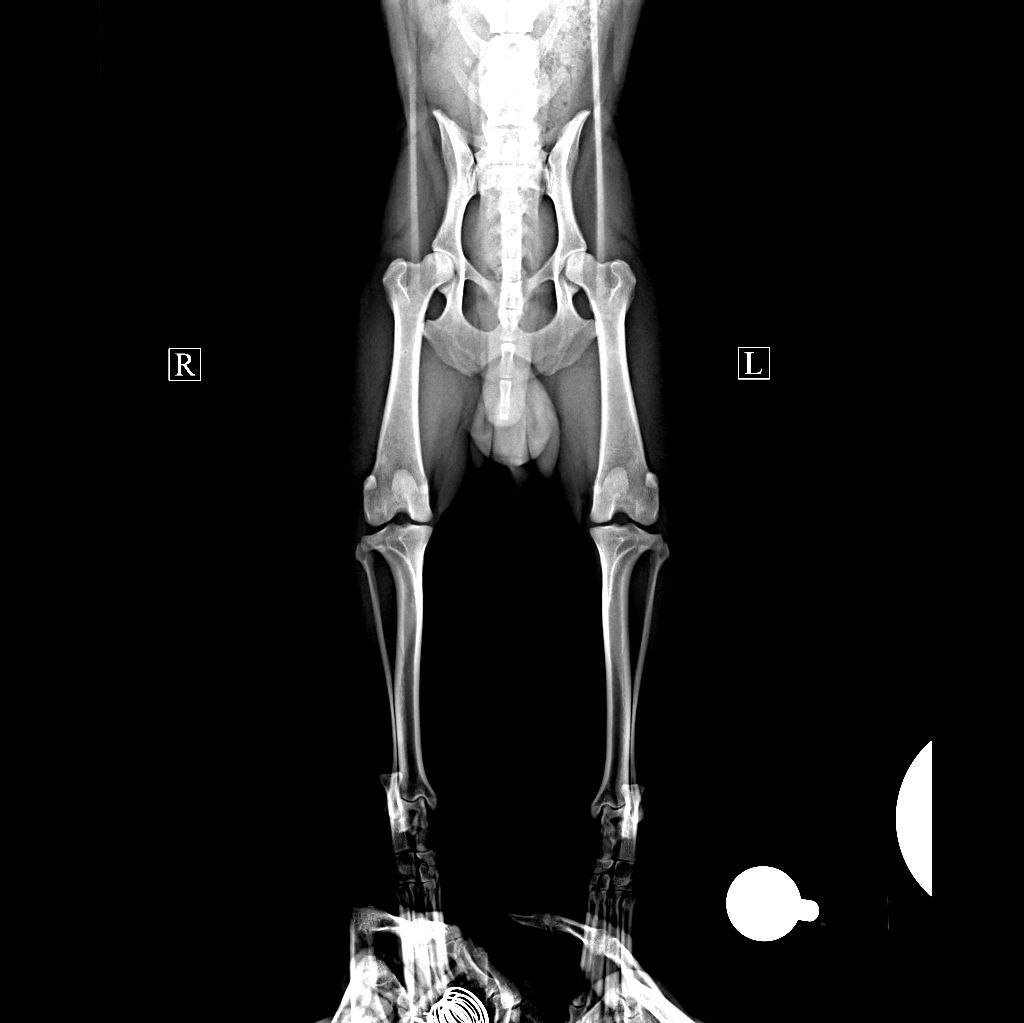

26.12.2023 - вскрылся свищ на тазовой кости

Завтра УЗИ и на четверг записались к Дудкину по лапе.

Мы не согласны и рентген надо сделать.